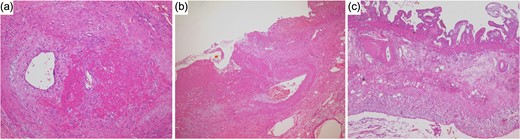

Histopathological findings showed necrosis and bleeding of the gallbladder wall in places. At the area of the gallbladder with bleeding, infiltrations of inflammatory cells around the blood vessels and vascular rupture was seen in the muscularis propria (Fig. 2a and b). However, little inflammatory cell infiltration was observed in the areas of the gallbladder without bleeding (Fig. 2c).

Histopathological findings. (a) At the area of the gallbladder with bleeding, infiltrations of inflammatory cells around the blood vessels was seen in the muscularis propria. (b) Vascular rupture was seen in the muscularis propria. (c) Little inflammatory cell infiltration was observed in the areas of the gallbladder without bleeding.